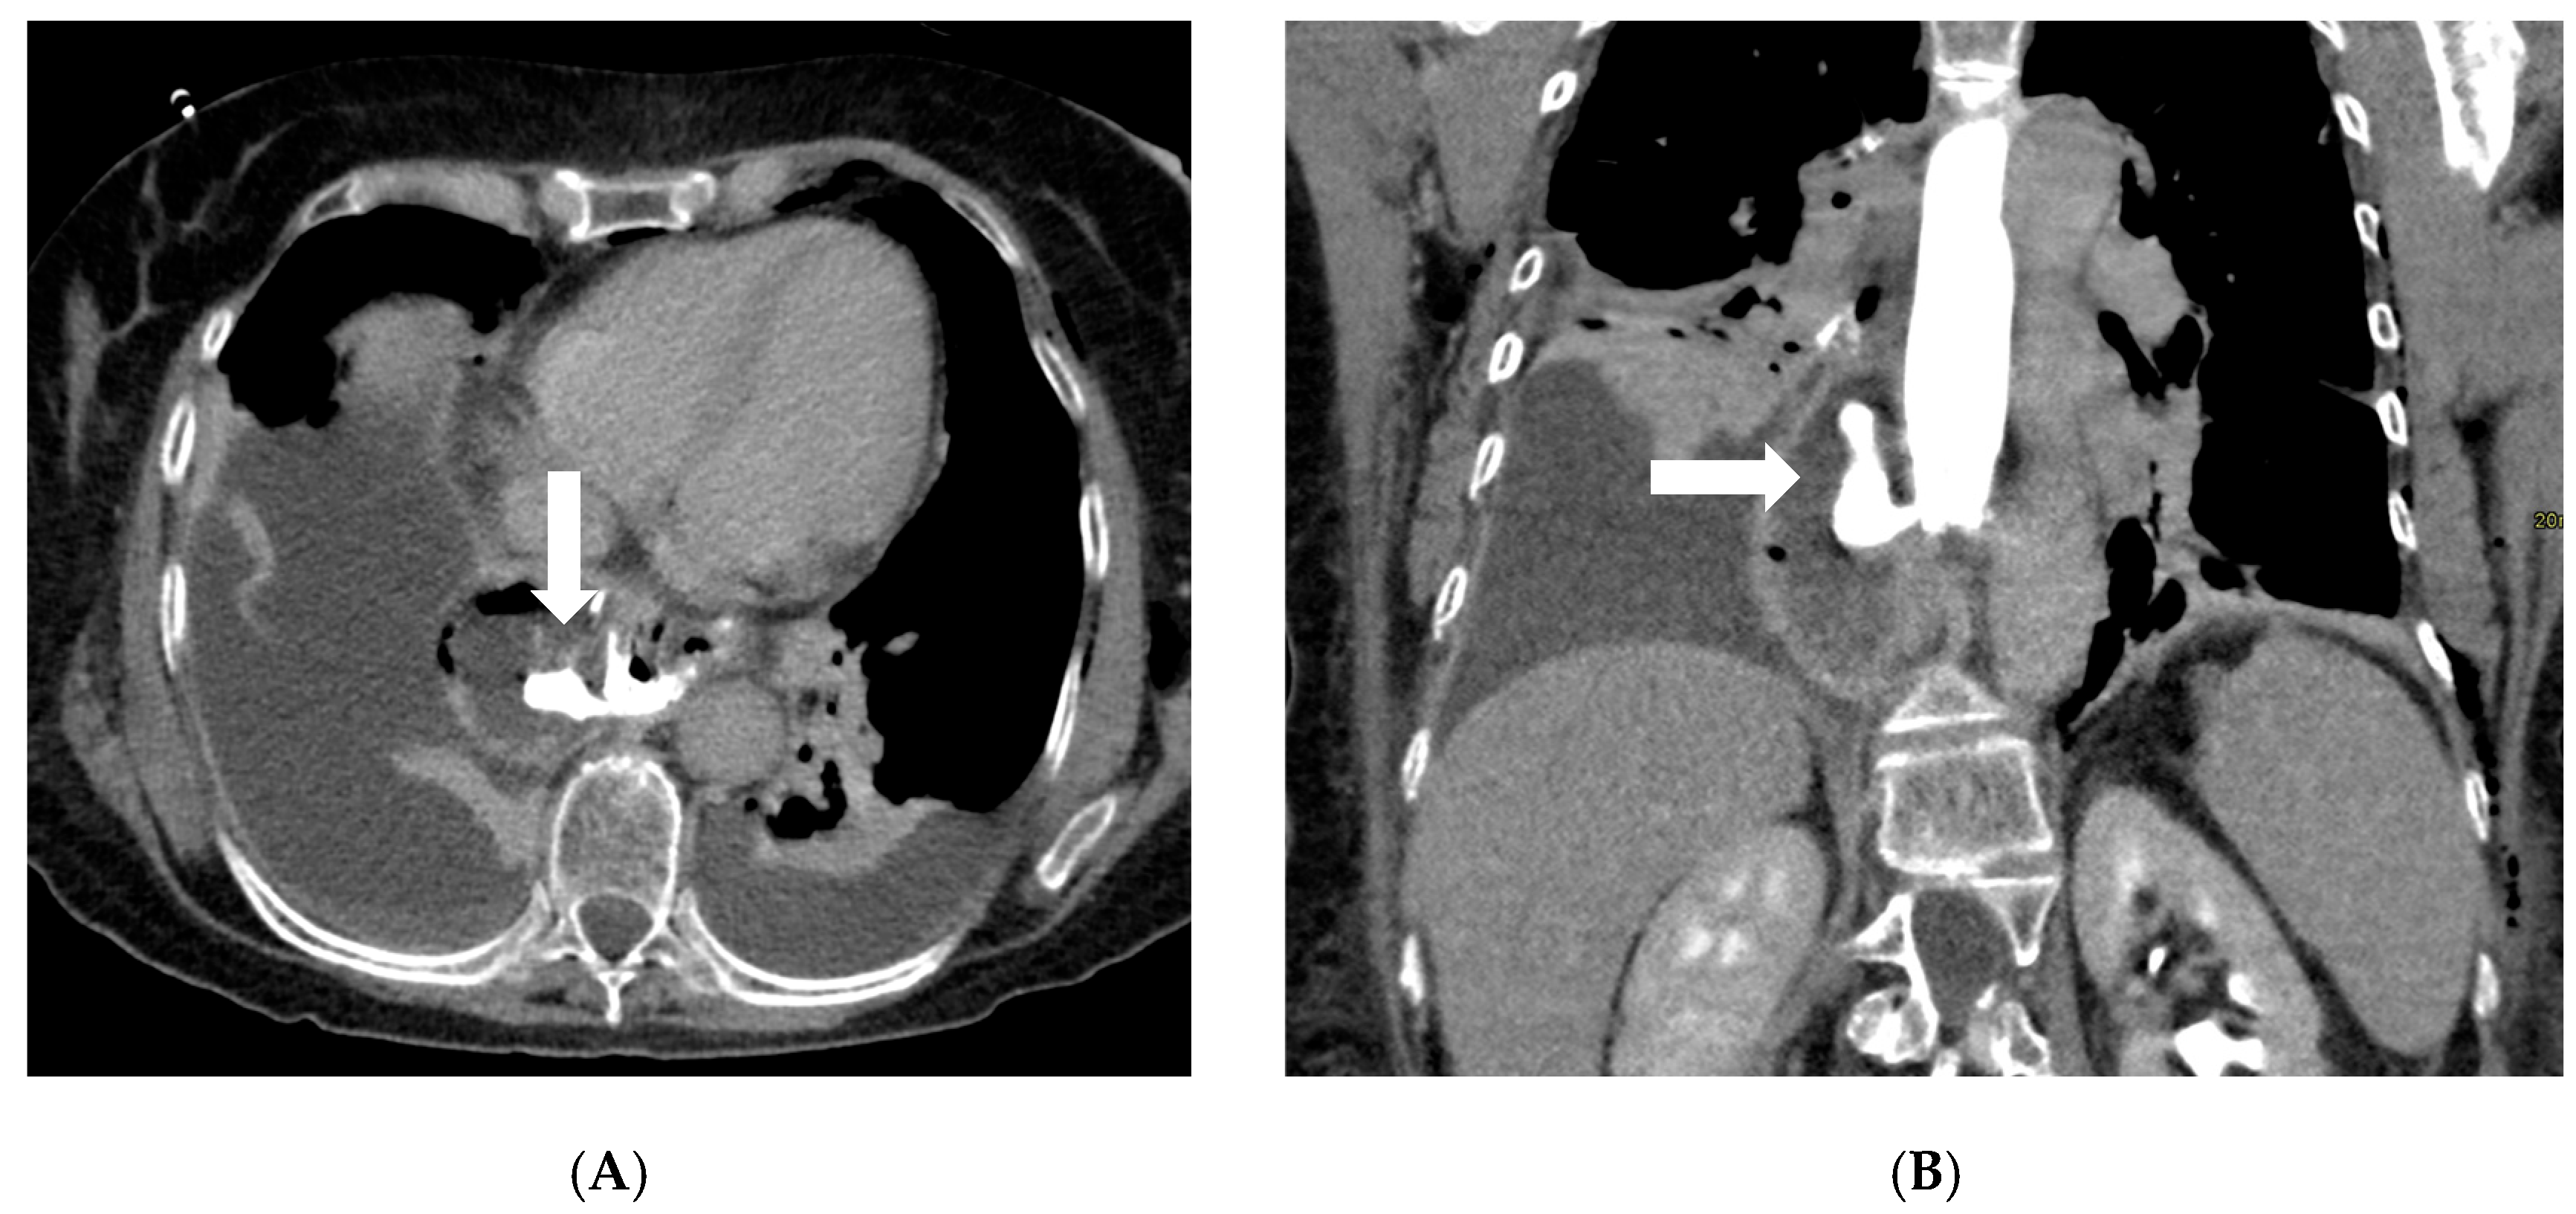

Figure 2.

Axial (A) and coronal (B) post-contrast CT scans in a patient on postoperative day 3 following gastric bypass with esophagojejunostomy positioned in the mediastinum (history of sleeve gastrectomy). An esophagojejunal feeding tube is in place. To the right of the esophagojejunal anastomosis, a hypodense collection with internal air components is visible. After oral administration of water-soluble contrast, a posterior dehiscence of the anastomosis is demonstrated, with extraluminal contrast leakage accumulating within the previously described collection (arrows). The copyright of this figure belongs to the authors.